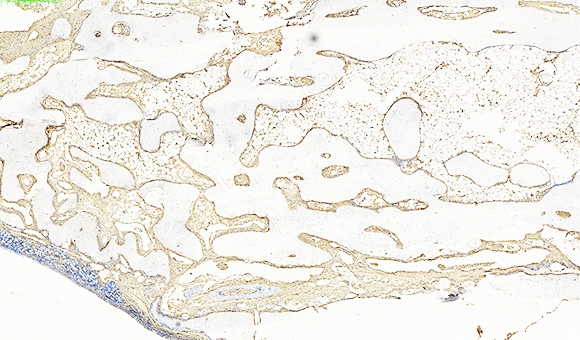

免疫组化技术,即免疫组织化学技术,是一种利用抗原与抗体特异性结合的原理,通过化学反应使标记抗体的显色剂着色,从而可以对组织细胞内的抗原进行定性、定位及相对定量研究的科学方法。

免疫组化技术的核心原理是抗原与抗体的特异性结合。抗体是一种免疫系统产生的特殊分子,能识别和结合特定的目标分子,如细菌、病毒或肿瘤细胞等。免疫组化技术利用了抗体的这种特性,通过标记荧光染料或酶标记等,将目标分子显示出来。免疫组化的结果通常以染色或未染色的形式表示,可以帮助医生判断疾病的状态和类型。